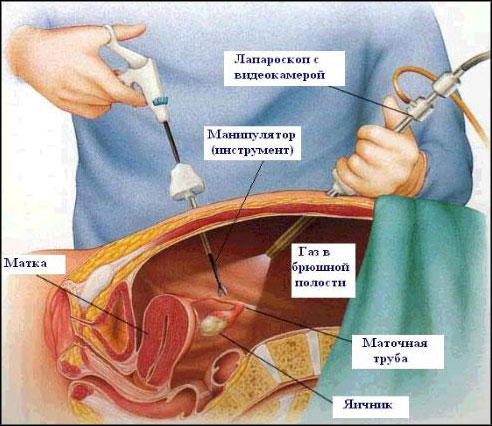

Современные методы лапаротомии и миомэктомии